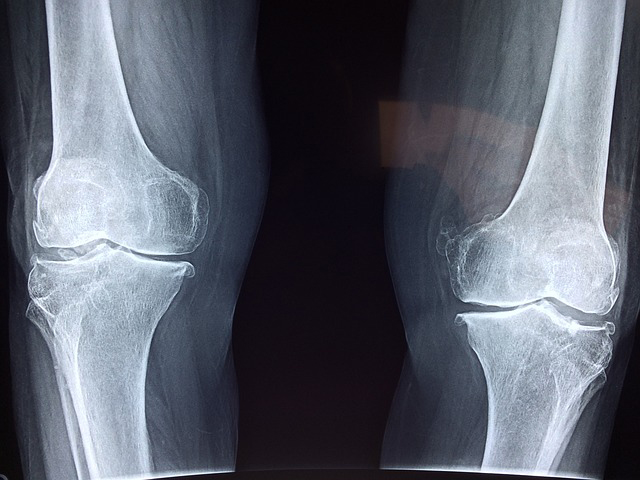

Más del 9% de la población española depende, para llevar una vida normal, de un producto ortopédico. Eso, en cifras de nuevo, representa a casi cuatro millones de personas que demandan, cada vez más, un tipo de producto que se adapte a la perfección a ellos.

La tecnología, con las impresiones 3D también a la cabeza, están suponiendo toda una revolución capaz de preparar productos y prótesis que encajan sin problema en cada usuario.

Pero, ¿qué es lo que hace de la personalización un avance increíble? Desde Orto Ruíz, ortopedia técnica con servicios personalizados, lo explican de forma sencilla. “Cada persona es única, y sus necesidades médicas y ortopédicas también lo son. La ortopedia a medida permite crear dispositivos adaptados a las medidas y requerimientos específicos de cada paciente, asegurando un ajuste perfecto y un mayor confort” explican.

De esta forma, se consigue una mayor eficacia de los dispositivos, del tratamiento y, por extensión, una mejora significativa de la movilidad y funcionalidad. Este tipo de diseños se adaptan a los cambios que puedan ir surgiendo en la condición de cada paciente, realizando ajustes y modificaciones que, gracias a técnicos especializados, evitan tener que reemplazar toda la aparatología en cada momento.

Estas nuevas técnicas, más allá de ser la mejor respuesta para casos complejos que necesitan productos a medida, consigue una mayor comodidad y una reducción de los problemas secundarios que puedan derivar en su uso como la fricción, que acaba provocando úlceras o incluso malas posturas y lesiones secundarias por el mal ajuste.

“En muchos casos son dispositivos que se van a usar de forma temporal durante la rehabilitación y recuperación de una lesión. Colaborar con el proceso para restaurar esa funcionalidad y fuerza debe ser el objetivo de cualquier ortopedia. De hecho, cuando se demora en el tiempo o acaba siendo permanente, el objetivo siempre debe ser mejorar la independencia y la calidad de vida” cuentan.

Contar con una ortopedia que, a su vez, disponga de taller donde ajustar cada elemento al máximo, personalizar sus formas y acompañar en el desarrollo y uso del mismo al paciente es clave para conseguir, de verdad, el objetivo de todo este sector médico.